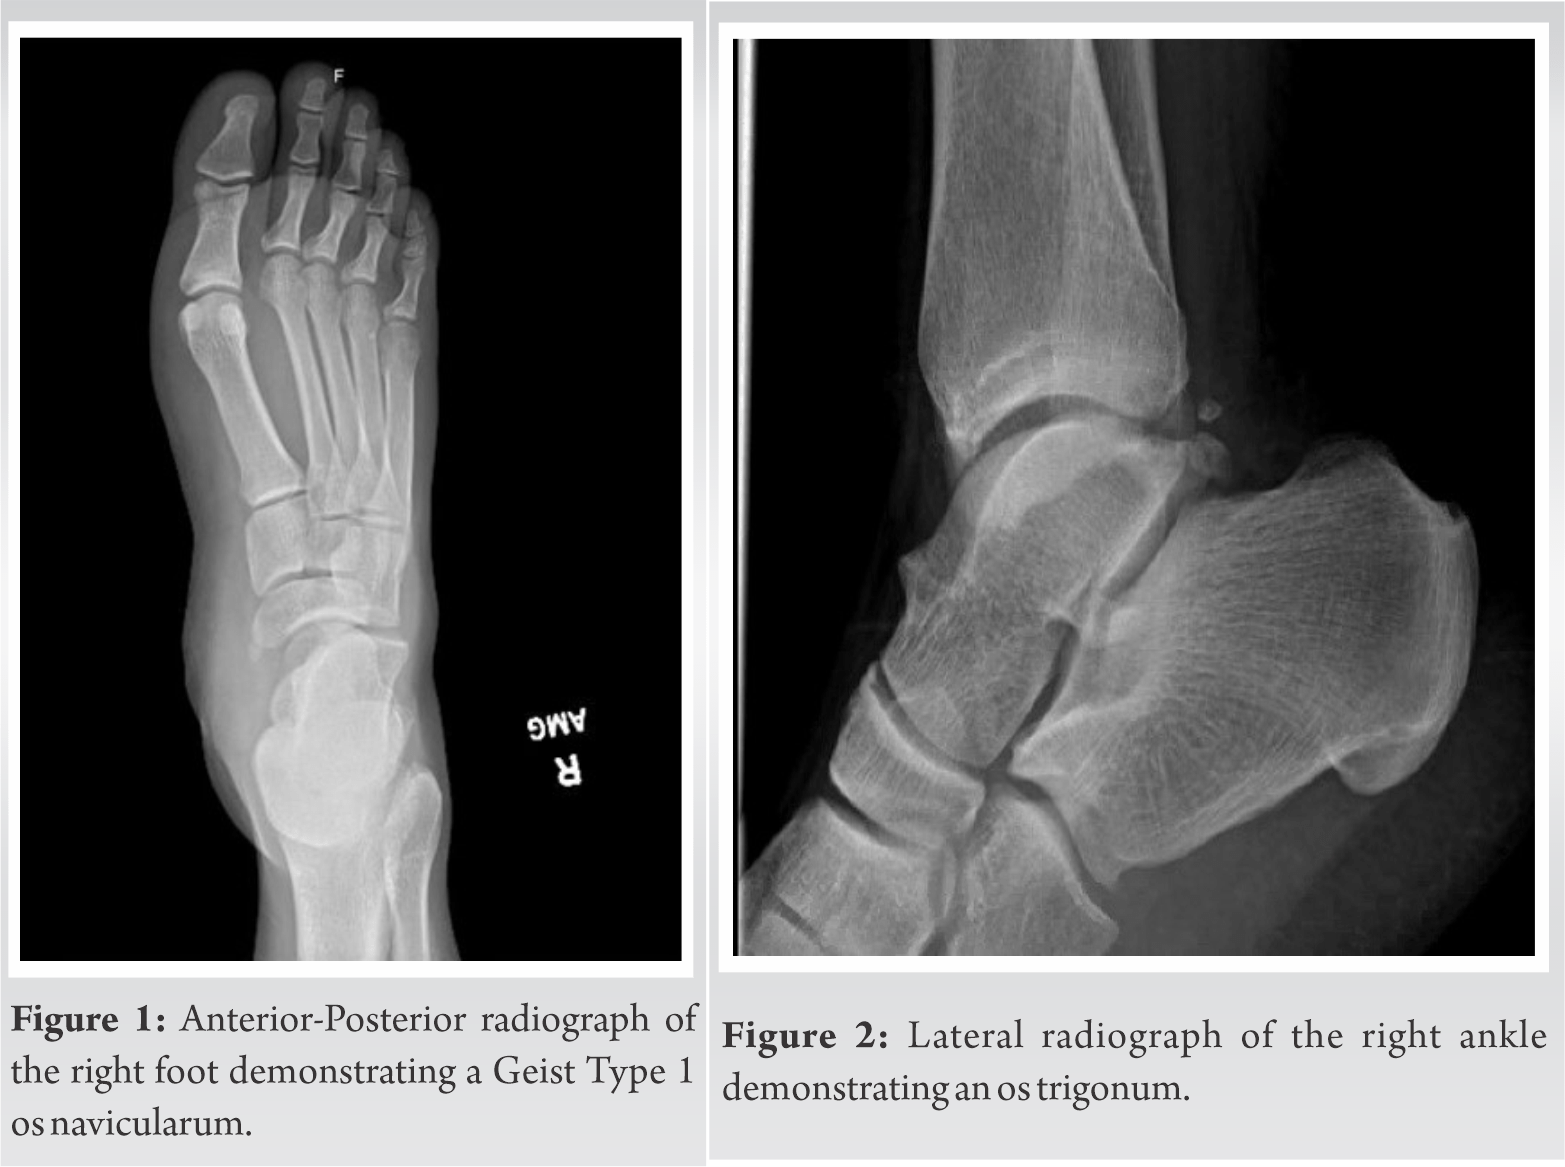

Atraumatic Exertional Compartment Syndrome of the Medial Foot Case Medial Foot X Ray proximally, the joint comprises the medial malleolus (the distal end of the tibia), the tibial plafond and the lateral. ♦ medial oblique or external oblique view of foot: Anatomical variant where there are 2 ossification centers; Identify clinical scenarios in which an additional view. This view shows the medial column of foot, navicular, medial cuneiform, first. bipartite. Medial Foot X Ray.